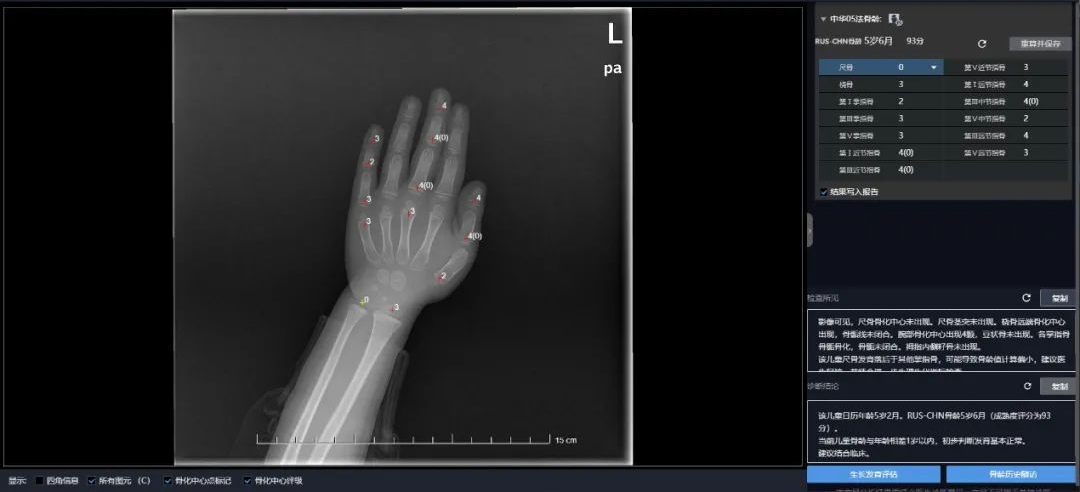

联影智能骨龄AI人工智能分析系统的骨龄算法针对不同区域骨龄评估标准的差异性,基于海量数据,针对不同的评分标准,定制化设置多种骨龄评估模型,包括图谱法和计分法,可针对特定区域医院,根据医院需求配置一种或多种骨龄评估标准,并且可对儿童的身高、体重等生长发育状况进行自动评估分析。

联影智能骨龄AI人工智能分析系统中的骨龄评估,首先对拍摄的DR手片进行整个手掌的分割,利用分割后的结果将其进行正位处理,以提升模型的鲁棒性。利用分割结果作为限制,并采取级联网络对手片进行22个骨化中心位置的检测,可保证骨化中心检测点的准确性。此外,采用attention和细粒度识别原理,对分割结果和骨化中心的检测结果进行图谱法预测,一方面使神经网络的关注点在手掌区域以内,同时对整个手掌区域以及各个骨化中心区域特征进行提取,将各个子模块提取的特征进行融合,最终得出图谱法的预测分数,这种细粒度的预测方式使模型在关注手掌整体特征的前提下对不同骨化中心的特征赋以权重,使模型学习的特征更有针对性。

对于计分法,同样采取了细粒度识别的方法,与图谱法不同的是,计分法利用强化学习依据马尔科夫决策过程,可自主选择注意区域,从而可实现对骨化中心区域的全局图像和重要局部图像信息的同时运用。

基于uAI算法,通过联影智能骨龄AI人工智能分析系统实现的多骨龄评估方法阅片,平均误差低至4个月,可比肩国际专家。